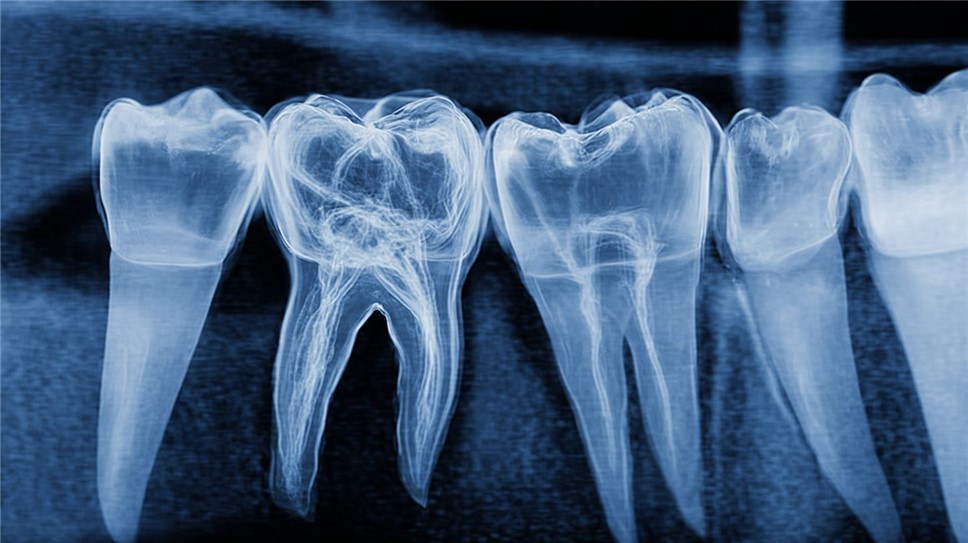

При хроническом пульпите боль становится тупой и ноющей, возникая спонтанно или при надавливании, и может иррадиировать в ухо или челюсть. Ограничением самостоятельной оценки является субъективность ощущений: гипотеза о пульпите требует подтверждения рентгеновским снимком для оценки распространения инфекции. В Санкт-Петербурге, согласно нормам Сан Пи Н 2.1.3.2630-10, клиники используют цифровую радиографию для точной визуализации.

Схематическое изображение зон боли при различных формах пульпита.

Инструментальные методы усиливают диагностику: рентгенография в прицельной проекции выявляет периапикальные изменения в 60% хронических случаев. Цифровой рентген, внедрённый в 90% российских клиник по стандартам Росздравнадзора 2025 года, снижает дозу облучения на 70% и позволяет оценить глубину кариеса. Для сложных анатомий, как у многокорневых зубов, применяется конусно-лучевая компьютерная томография (КЛКТ), точность которой достигает 95% по данным исследований в Новосибирском НИИ.

Пример рентгенограммы, демонстрирующей изменения в области корня зуба при пульпите.